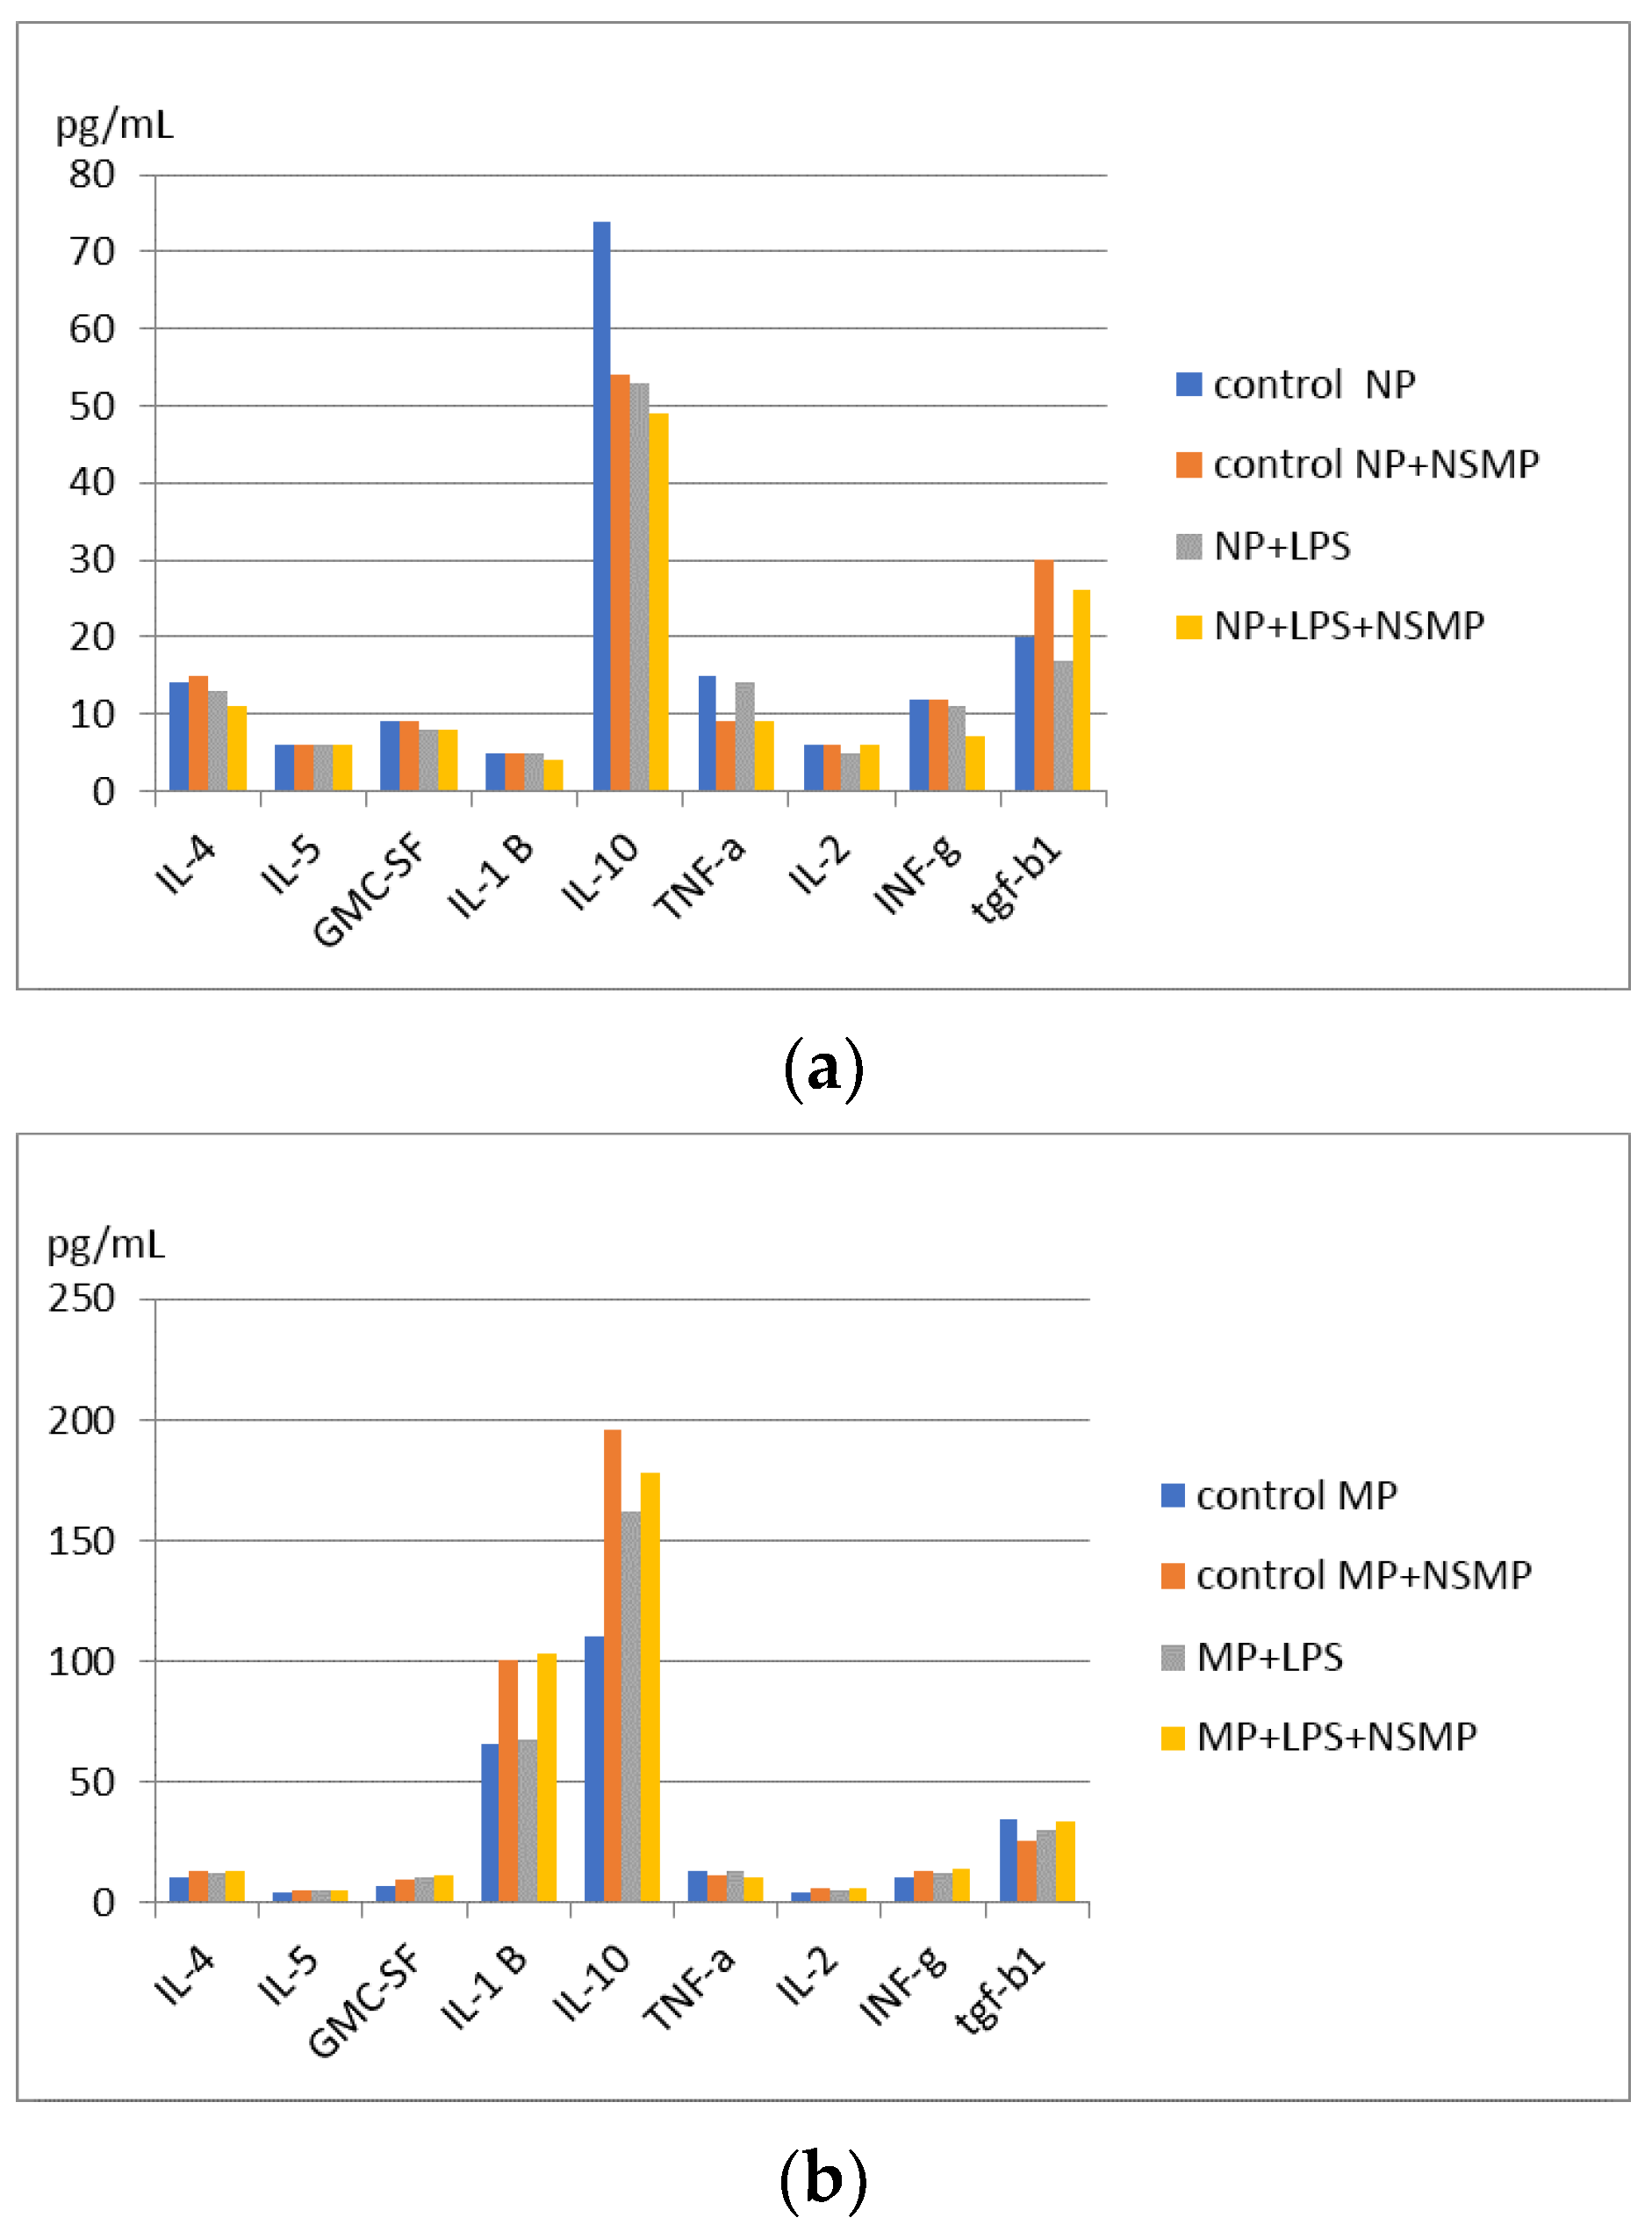

2.2. Results of Cytokine Production Studies, When Co-Culturing NSMP with Inflammatory Peritoneal Cell Exudate Obtained in the Mice Model of C57Bl/6J Inbred Line

| Group 1 Peritoneal Cellular Exudate Obtained on the First Day | Group 2 Peritoneal Cellular Exudate Obtained on the Third Day | ||||||

|---|---|---|---|---|---|---|---|

| Control 1 | Control 2 | Study 3 | Study 4 | Control 5 | Control 6 | Study 7 | Study 8 |

| Neutrophils (NP) | NP+ NSMP | NP+ LPS | NP+ LPS+ NSMP | Macrophages (MP) | MP+ NSMP | MP+ LPS | MP+ LPS+ NSMP |